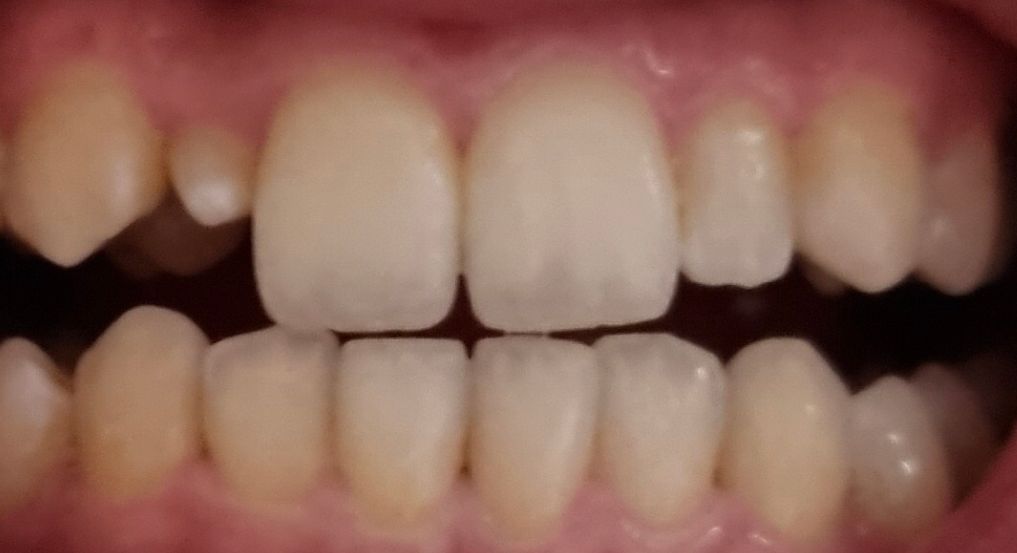

어렸을때 이빨을 뽑았는데 그 이후로 앞니 옆에 이빨 하나가 조금만 자라고 그 이후로 자라질 않아요..ㅠㅠ

이 정도 크기의 왜소치는 어떻게 씌우는게 좋을까요?

• 2번 째 사진

현재 치아가 작아서 미관상 보기가 좋지 않은 경우 레진을 이용하여 치아모양을 보완할수 있으며 라미네이트는 치아삭제가 필요로 되기에 치과에 방문하여 보다 정확한 상태를 확인후 치료방향을 결정하길 바랍니다.

현재와 같은 경우에는 크라운 등을 시행하게 되면 공간이 부족할 수 있어 보입니다. 또한 해당 치아만 수복하게 될 경우에 주변 치아와 정확히 색을 맞추기 힘들어 권하지 않으며 라미네이트 등을 하는 것이 맞아 보입니다. 보통 왜소치가 있거나 전치부 심미 문제가 있을 때 라미네이트가 대안이 될 수 있습니다.

사진으로 봤을때 치아가 굉장히 작습니다

레진이나 라미네이트로는 쉽지 않을듯 하고, 크라운을 씌우는게 가장 좋을것으로 보입니다.